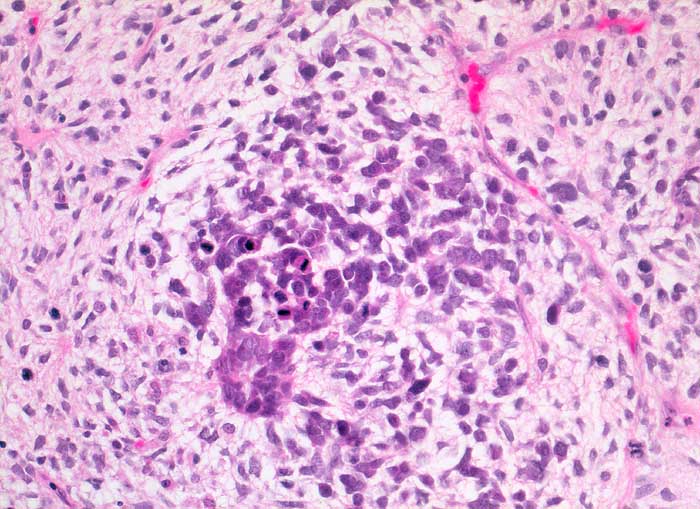

PathoPic ID 5385 - maligner Müller'scher Mischtumor: Sarkomkomponente

maligner Müller'scher Mischtumor: Sarkomkomponente

maligner Tumor

Ovar

Genitalorgane, weiblich

Sarkomatöse Komponente mit zahlreichen Mitosen

Ovarialkarzinom

Histologie

200